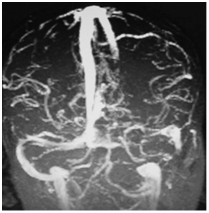

MR venography, which can demonstrate the loss of signal and the absence of flow in the sinus, has proven to be more sensitive diagnostic tool in identifying the thrombus (Figure 14).

Figure 14 Magnetic resonance venography image demonstrating lack of flow in the left lateral sinus.